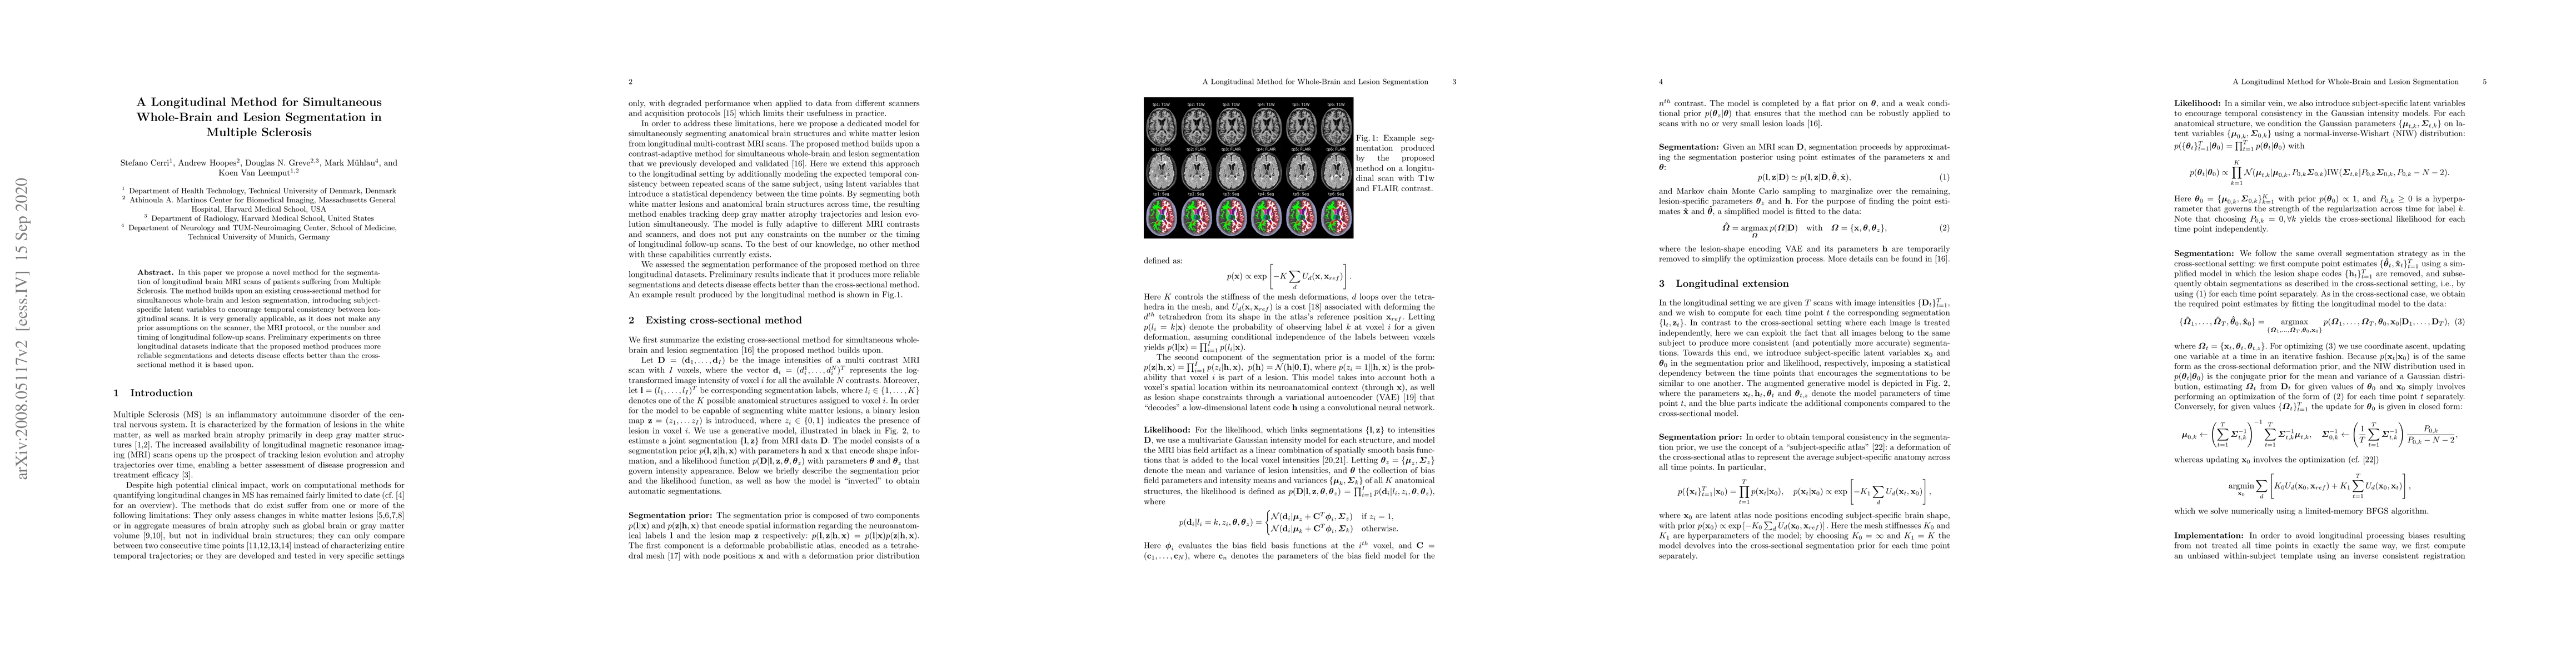

In this paper we propose a novel method for the segmentation of longitudinal brain MRI scans of patients suffering from Multiple Sclerosis. The method builds upon an existing cross-sectional method for simultaneous whole-brain and lesion segmentation, introducing subject-specific latent variables to encourage temporal consistency between longitudinal scans. It is very generally applicable, as it does not make any prior assumptions on the scanner, the MRI protocol, or the number and timing of longitudinal follow-up scans. Preliminary experiments on three longitudinal datasets indicate that the proposed method produces more reliable segmentations and detects disease effects better than the cross-sectional method it is based upon.